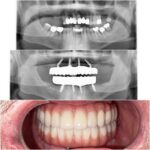

If you are searching for exceptional cosmetic dentists in a state-of-the-art dental practice in Roseville, California. You have found the right place. We also service the greater Sacramento area. As cosmetic dentists, Dr. Kwan and Dr. Hsu will provide you with a beautiful and functional smile that you’ve always dreamed of. At Nu Smile Roseville Dental, we pride ourselves on providing all guests with the most advanced cosmetic dentistry techniques and procedures, performed with the most cutting-edge technology, in a comfortable, relaxed setting.

Our friendly, knowledgeable staff will make you feel at home right away in our family-oriented office. Modern facilities such as digital X-rays and intra-oral cameras help ensure the best of care for your dental health. Patient records are fully computerized for fast access and maximum protection of your privacy. Our small, private Roseville practice is designed to efficiently serve your needs. We offer a wide range of general, restorative, and cosmetic dental services. We also have a library of Caesy Educational System multimedia presentations that clearly explain many dental procedures.